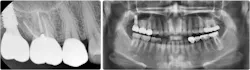

If the bony height defect is not significantly large (residual bone height over 4 mm), a crestal approach is usually adopted. This involves accessing the sinus cavity directly through the dental implant site, typically during implant placement. The traditional osteotome technique, originally proposed in 1994 by Summers,1 involves manually tapping with a mallet specialized instruments into the bone to upfracture the sinus bone and forcibly create space (figures 1 and 2).

If more bone augmentation is required, the lateral window approach is often adopted as it provides better access and elevation of the sinus membrane. This involves drilling a bony window through a large flap raised on the posterior maxilla. However, this approach is more invasive and carries a greater risk of side effects ranging from extremely painful hematoma formations, infections, damage to the infraorbital neurovasculature, to, most commonly, perforations in the sinus membrane.